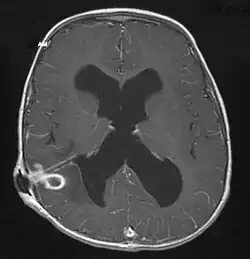

Brain abscess in a person with a CSF shunt. The abscess is the darker gray region in the lower left of the image (corresponding to the right parietal lobe). The lateral ventricles are visible in black in the center of the brain, adjacent to the abscess.[1]

MRI (T1 with contrast) showing the ring-enhancing lesion. From a rare case report of an abscess formed as a complication of the CSF shunt. Jamjoom et al., 2009.[1]

The diagnosis is established by a computed tomography (CT) (with contrast) examination. At the initial phase of the inflammation (which is referred to as cerebritis), the immature lesion does not have a capsule and it may be difficult to distinguish it from other space-occupying lesions or infarcts of the brain. Within 4–5 days the inflammation and the concomitant dead brain tissue are surrounded with a capsule, which gives the lesion the famous ring-enhancing lesion appearance on CT examination with contrast (since intravenously applied contrast material can not pass through the capsule, it is collected around the lesion and looks as a ring surrounding the relatively dark lesion). Lumbar puncture procedure, which is performed in many infectious disorders of the central nervous system is contraindicated in this condition (as it is in all space-occupying lesions of the brain) because removing a certain portion of the cerebrospinal fluid may alter the concrete intracranial pressure balances and causes the brain tissue to move across structures within the skull (brain herniation).[14]

Ring enhancement may also be observed in cerebral hemorrhages (bleeding) and some brain tumors. However, in the presence of the rapidly progressive course with fever, focal neurologic findings (hemiparesis, aphasia etc.) and signs of increased intracranial pressure, the most likely diagnosis should be the brain abscess.[15]